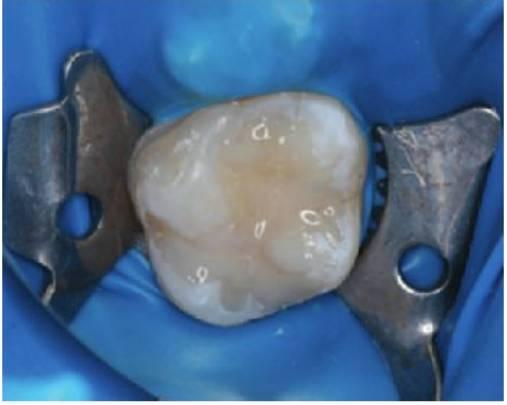

- Siempre que sea necesario, infiltrar anestesia local y aislar con dique de goma (fig. 5.3).

- El contorno de la cavidad debe rodear toda la extensión de la lesión cariosa. No es necesaria una extensión por prevención. Tampoco suele ser necesaria una pequeña cola de milano oclusal en las restauraciones interproximales. Sin embargo, la retención de las cavidades proximales mínimas puede conseguirse practicando surcos en la dentina con una fresa redonda muy pequeña (tamaño Yi) (fig. 5.4).